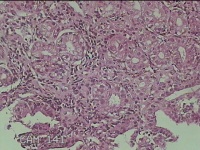

胃角粘膜

性别

男

年龄

29岁

临床诊断

复合性溃疡;慢性胃炎

一般病史

上腹部疼痛1个月余。

标本名称

大体所见

灰白粉红色组织小米大2团。

良性病变。